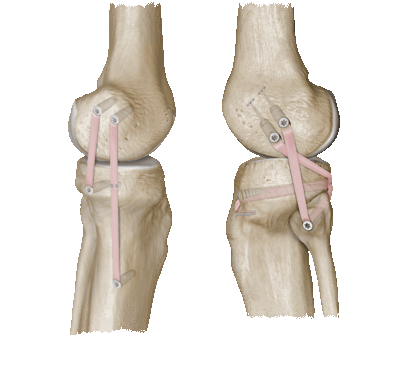

Если операция по реконструкции связок проведена хорошо, то они становятся не менее прочными чем до операции.